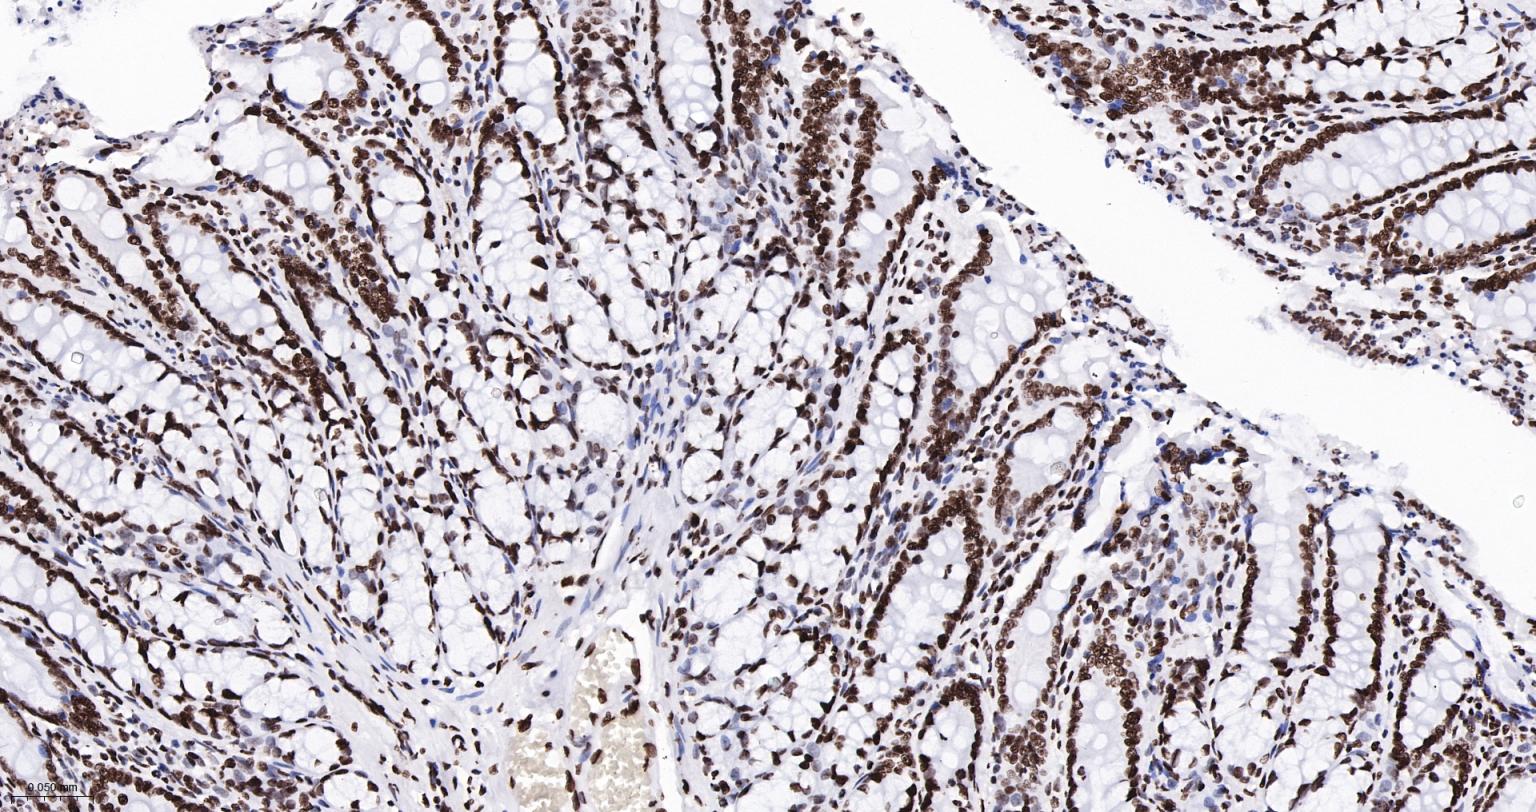

Paraformaldehyde-fixed, paraffin embedded Human Colon Cancer; Antigen retrieval by boiling in sodium citrate buffer (pH6.0) for 15 min; The section was incubated with Acetyl-Histone H3(K9) Monoclonal Antibody, Unconjugated (bsm-63244R) at 1:200 overnight at 4°C, followed by conjugation to the bs-0295G-HRP and DAB (C-0010) staining.